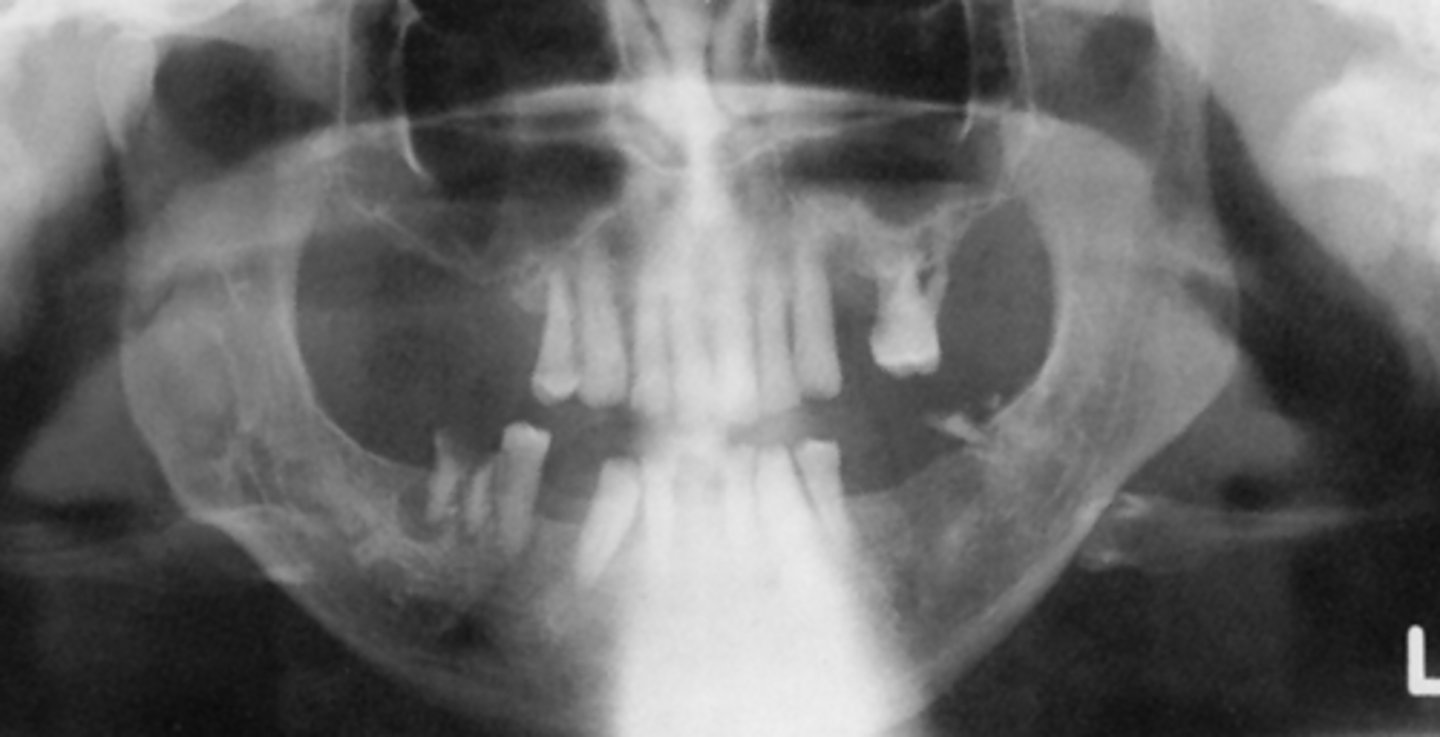

B) double real image

The structures outlined in green indicate what type of image?

A) real image

C) ghost image

The structures outlined in blue indicate what type of image?

The structures outlined in orange indicate what type of image?

B) ghost

The white arrows represent the ___ hard palate

A) real

The black arrows represent the ___ hard palate

B) ghost left mandible

The black triangles represent the ___

A) real left mandible

C) real right mandible

D) ghost right mandible